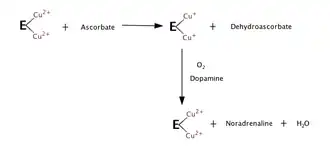

DBH is a 290 kDa copper-containing oxygenase consisting of four identical subunits, and its activity requires ascorbate as a cofactor.[5]

Based on the observations of what happens when there is no substrate, or oxygen, the following steps seem to constitute the hydroxylation reaction.[6][7]

Although details of DBH mechanism are yet to be confirmed, DBH is homologous to another enzyme, peptidylglycine α-hydroxylating monooxygenase (PHM). Because DBH and PHM share similar structures, it is possible to model DBH mechanism based on what is known about PHM mechanism.[8]